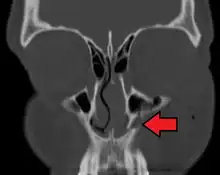

- the maxillary sinus

The maxillary sinus appears as a shallow groove on the nasal surface of the bone about the fourth month of development, but does not reach its full size until after the second dentition.

The maxillary sinus presents the appearance of a furrow on the lateral wall of the nose. In the adult the vertical diameter is the greatest, owing to the development of the alveolar process and the increase in size of the sinus.